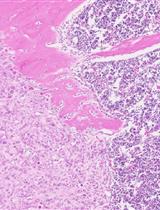

Both at the development stage and at the stage of evaluation of the efficiency of drug batches, it is important to confirm the mechanism of biological action. For gene therapy modalities, the development of such rapid assays is in demand [32]. Examination of spheroids by an immunofluorescence assay involving specific antibodies allowed us to analyze the expression of stem cell markers in order to confirm the targeted effect of miRNAs on the cancer cells within the spheroid. One hour after coincubation of a single-cell suspension of mouse liver cells and CD44– T47D_Red cells (the initial stage of spheroid formation), stand-alone differentiated tumor cells with the RFP+CD44–CD24+ phenotype were detectable within the spheroid (Figure 11).

Figure 11. Representative images of a spheroid at the formation stage at 1 h after coincubation of mouse liver cells and differentiated (CD44–) T47D_Red tumor cells. Cancer T47D_Red cells are red, CD44+ cells are green, CD24+ cells are magenta, and nuclei are stained with DAPI (blue).